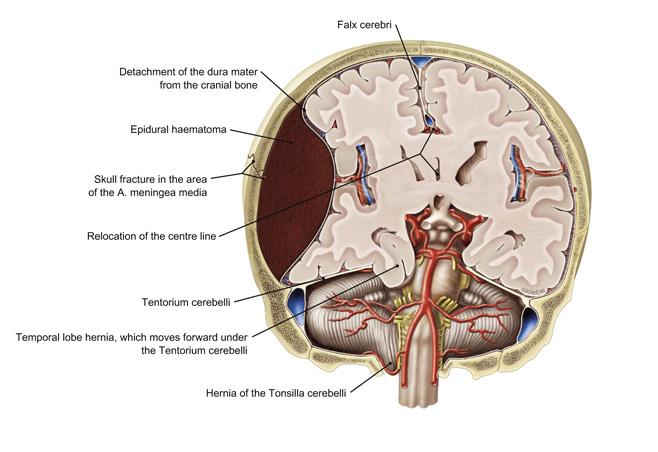

Fig 3.09b

C trauma

schedelfractuur epiduraal haematoom druk op hersenen stijgt